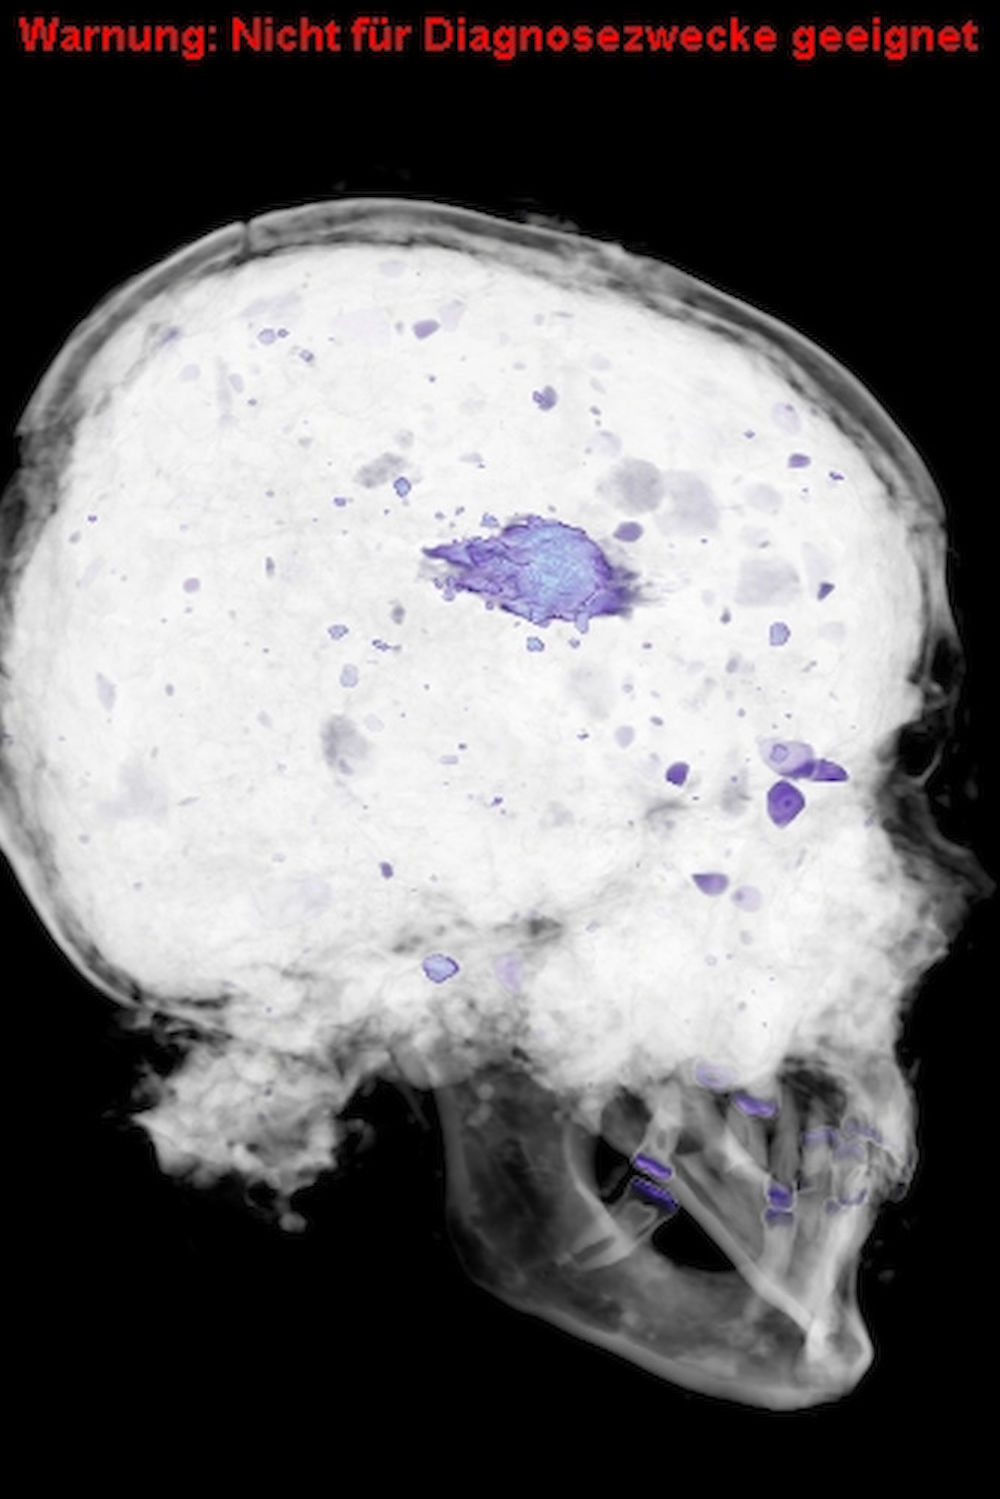

Silvio Brandt erklärt, was man anhand der Bilder erkennen kann (Slideshow):

„Es ging darum, Verletzungsmuster zu klären“, sagt der Oberarzt. 16 Schädel sind dafür von 2012 bis 2013 im CT untersucht worden. Dabei fand er heraus, dass einige der Männer hinterrücks erschossen wurden. „Die Befunde weisen Schussverletzungen von oben leicht nach unten führend auf, was darauf schließen lässt, dass einige der Soldaten zu Fuß vor Berittenen davongelaufen sind und von hinten getroffen wurden“, erklärt Brandt und zeigt dabei auf die CT-Aufnahmen auf dem Bildschirm in seinem kleinen, abgedunkelten Büro. Eine kurze Bewegung mit der Maus und die Aufnahmen eines Schädels laufen ab wie ein Film, so dass sich auch der Schussverlauf gut nachvollziehen lässt.

Außerdem lässt sich der Betrachtungswinkel der Aufnahme so verändern, dass der Knochen in 360-Grad-Perspektive betrachtet werden kann. Aufgrund der Untersuchungsmethode konnte auch das Sediment der Fundstelle in den Schädeln bleiben. „Das sind die lilafarbenen Flecken auf den Aufnahmen“, sagt Brandt. In einigen Schädeln steckten sogar noch die Bleikugeln – ganz oder zersplittert. Das lasse Rückschlüsse auf die Entfernung der Schützen zu, so Brandt. Simpel gesagt: Je näher man der Waffe war, desto mehr Durchschlagskraft hatte sie. Geschossen wurde damals, vor fast 400 Jahren, hauptsächlich mit Musketen und Pistolen.

Auch im Nachhinein sind noch Frakturen an den Knochen entstanden. Das Gelände des damaligen Schlachtfeldes, das von der alten Handelsstraße Via Regia und heutigen Bundesstraße B87 durchschnitten wird, wurde bis heute als Feld genutzt und ist teilweise bebaut. Schwere Landwirtschafts- und Baugeräte haben demnach ebenfalls Spuren hinterlassen, denn das Grab lag relativ nah an der Oberfläche. „Man kann anhand der Aufnahmen auch sehen, welche Verletzungen jünger sind und diese als Todesursachen ausschließen“, sagt Brandt.